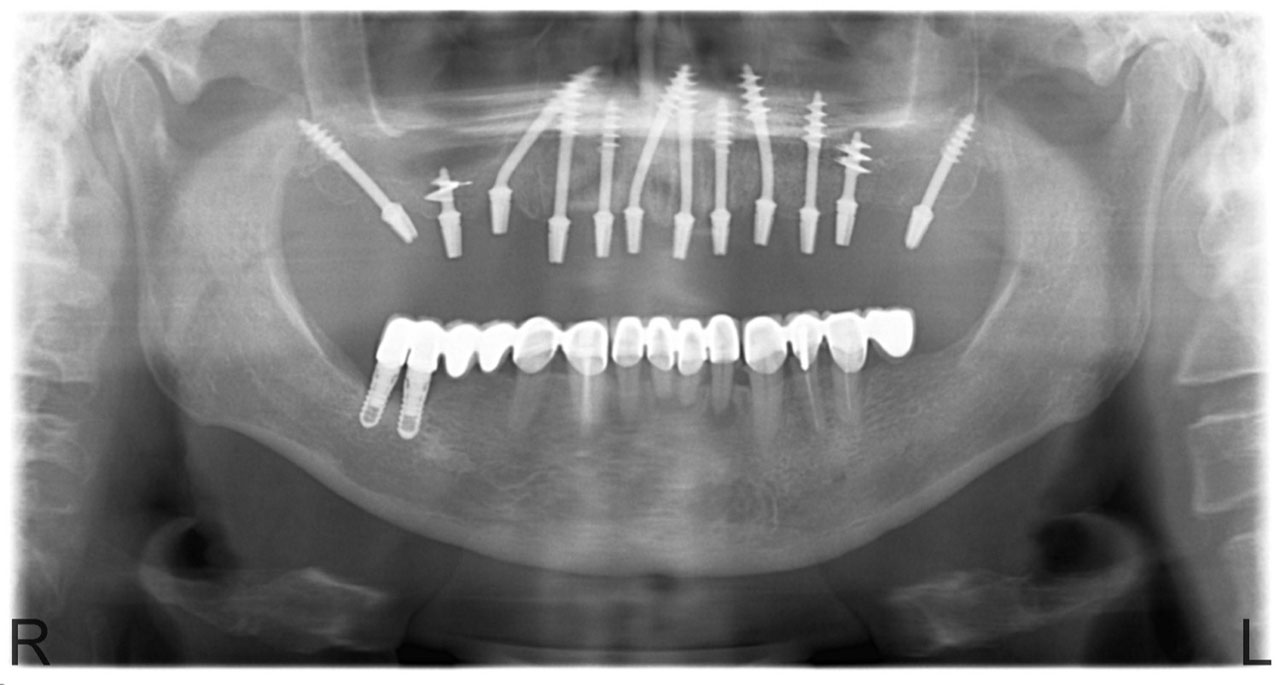

• esettanulmany-12

72 órával az alsó-felső állcsont teljes implantációs helyreállítása után, így mosolyog a páciens a beragasztott, fix hidakkal.

• esettanulmany-15

Nagykiterjedésű foghiány, és rossz gyökerek a felső állcsontban.

• esettanulmany-34

A felső állcsont teljes implantációs helyreállítása.